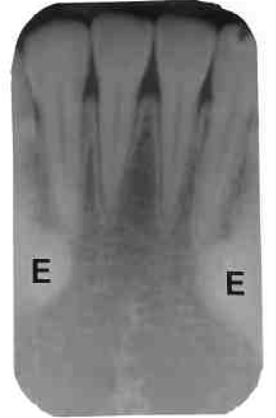

11. Which option is indicated by arrow E?

13. Arrow E showing which anatomical structure?

14. What is showing by E?

15. Arrow F showing which anatomical structure?

16. What is showing by E?